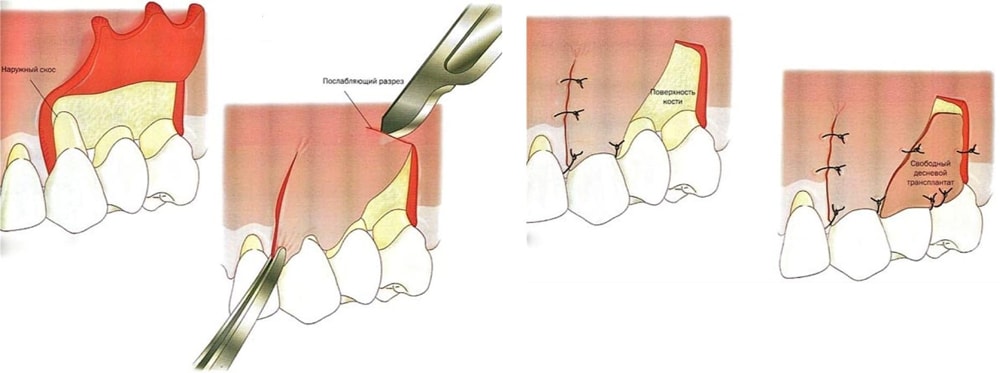

Реплантация зуба: Этапы и особенности операции